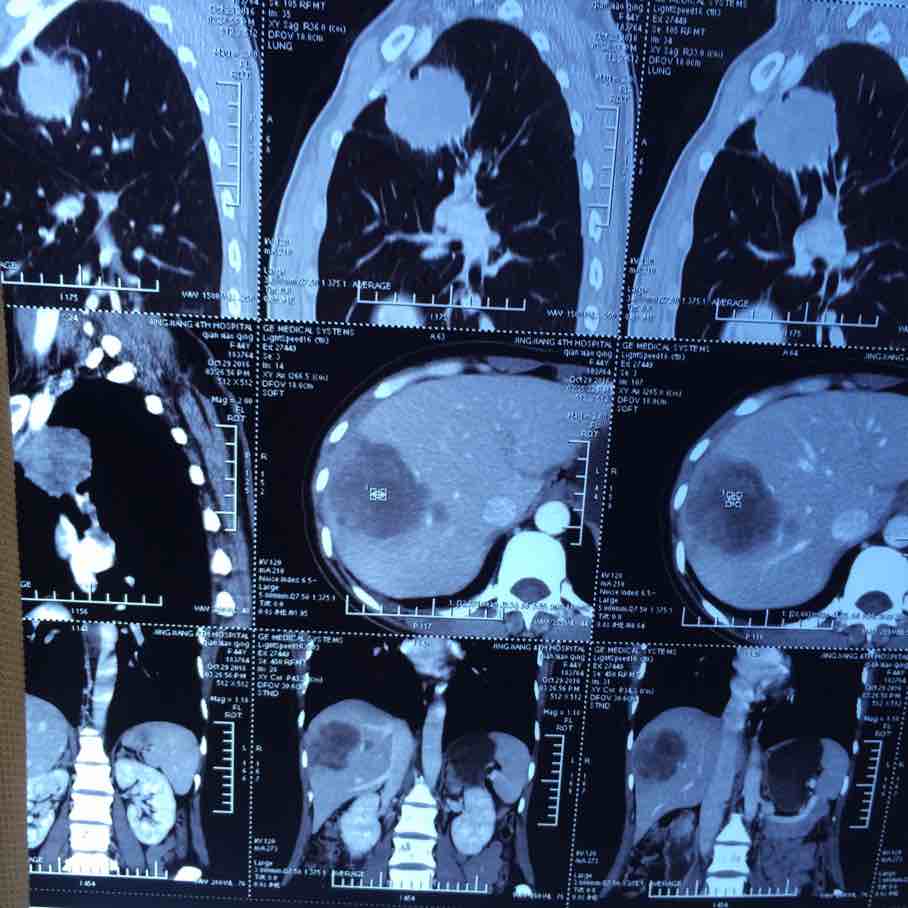

2017.10.29ct

陈医生,这是2016.10.26的ct看看拍的对不

举报

2017-10-31 10:10:21 有用(0)

回复(0)